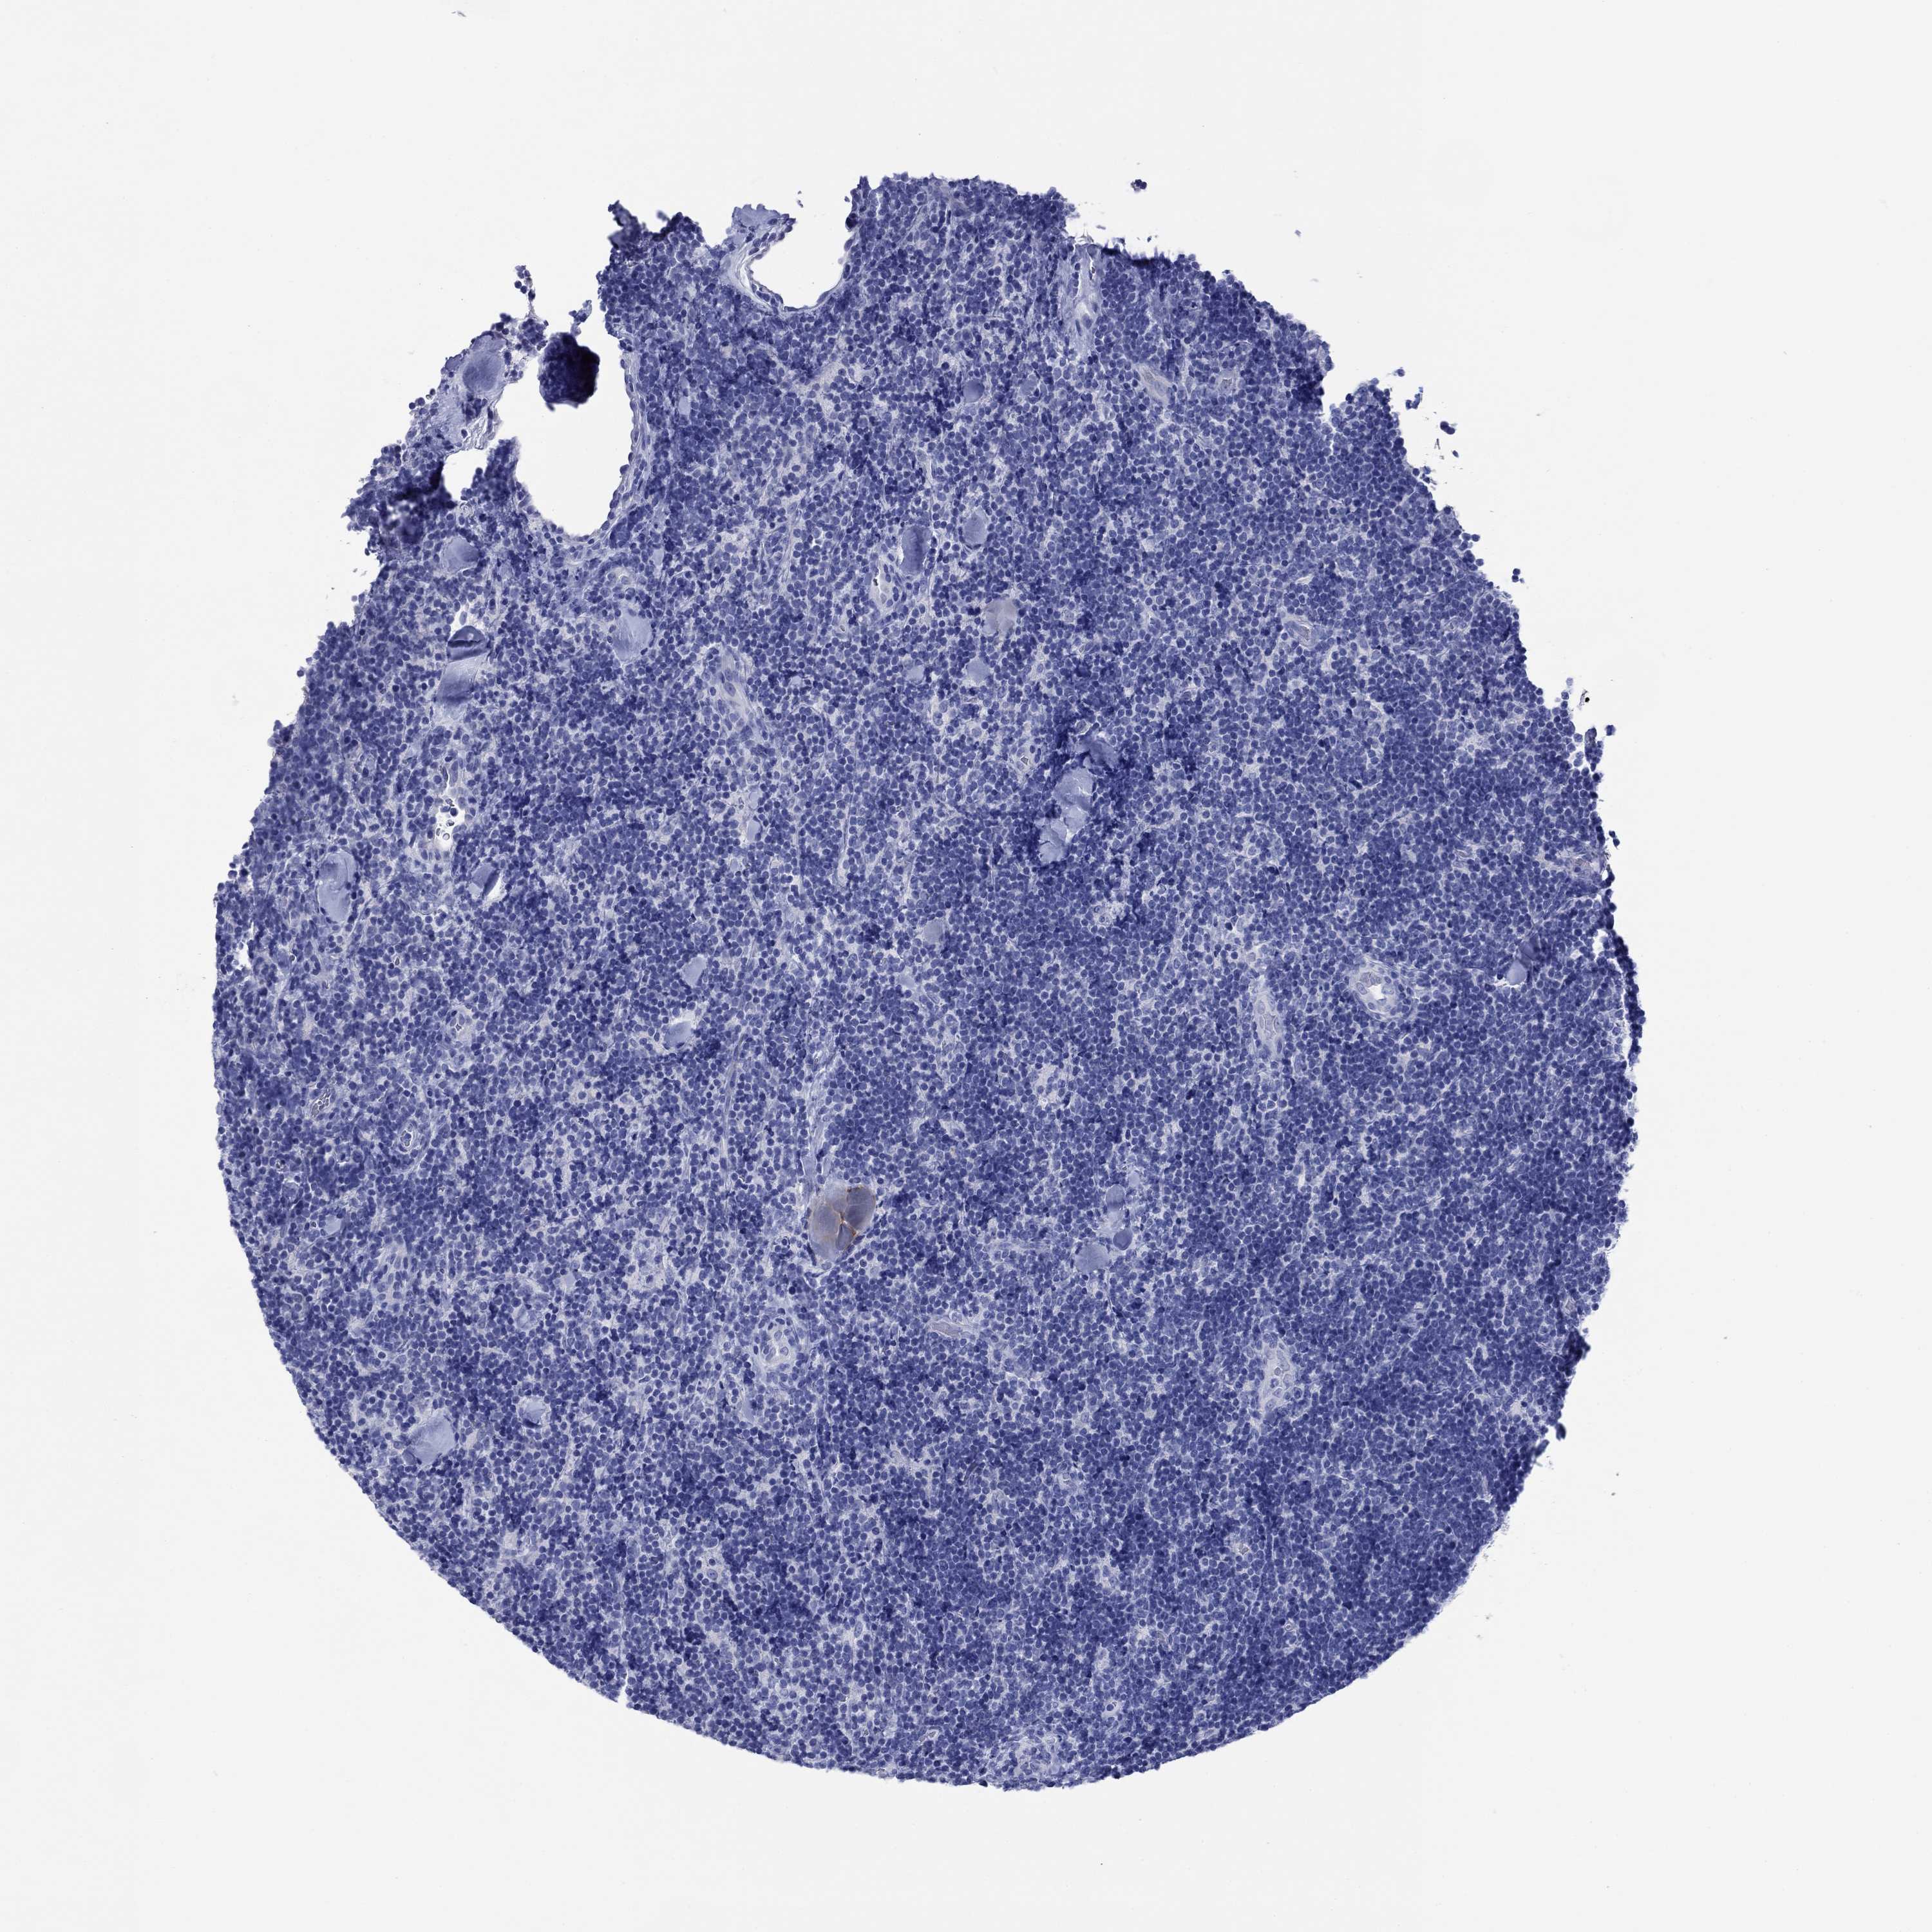

LYMPHOMA - Protein expressioni

A mouse-over function shows sample information and annotation data. Click on an image to view it in a full screen mode. Samples can be filtered based on level of antibody staining by selecting one or several of the following categories: high, medium, low and not detected. The assay and annotation is described here.

Antibody stainingi

Antibody staining in the annotated cell types in the current human tissue is reported as not detected, low, medium, or high, based on conventional immunohistochemistry profiling in selected tissues. This score is based on the combination of the staining intensity and fraction of stained cells.

Each image is clickable and will lead to virtual microscopy that enables deeper exploration of all samples and also displays staining intensity scores, fraction scores and subcellular localization as well as patient and tissue information for each sample.

Antibody HPA012911

Staining

Medium

Intensity

Moderate

Quantity

75%-25%

Location

Cytoplasmic/membranous

Malignant lymphoma, non-Hodgkin's type, High grade